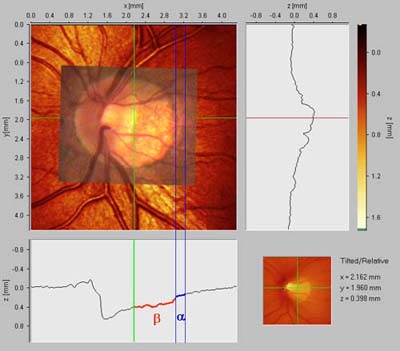

Peripapilární atrofie

Před 100 lety Elschnig a Bucklers rozpoznali souvislost mezi peripapilární atrofií a glaukomem a cirkulární peripapilární atrofii v pozdních stadiích glaukomové neuropathie nazvali "halo glaucomatosus". Oftalmoskopicky jsou patrné dvě zóny: beta je centrální, alfa periferní.

Zóna ALFA:

nepravidelná hypo a hyperepigmentace a ztenčení chorioretinální tkáně. Je projevem nepravidelností pigmentu retinálního pigmentového epitelu. Způsobuje relativní skotom.

Zóna BETA:

je světlejší zóna s viditelnou sklérou a velkými cévami cévnatky.

Nepřímá úměra jejího rozsahu k výši nitroočního tlaku: Čím vyšší tenze, tím menší atrofie. Čím nižší tenze, tím větší atrofie.